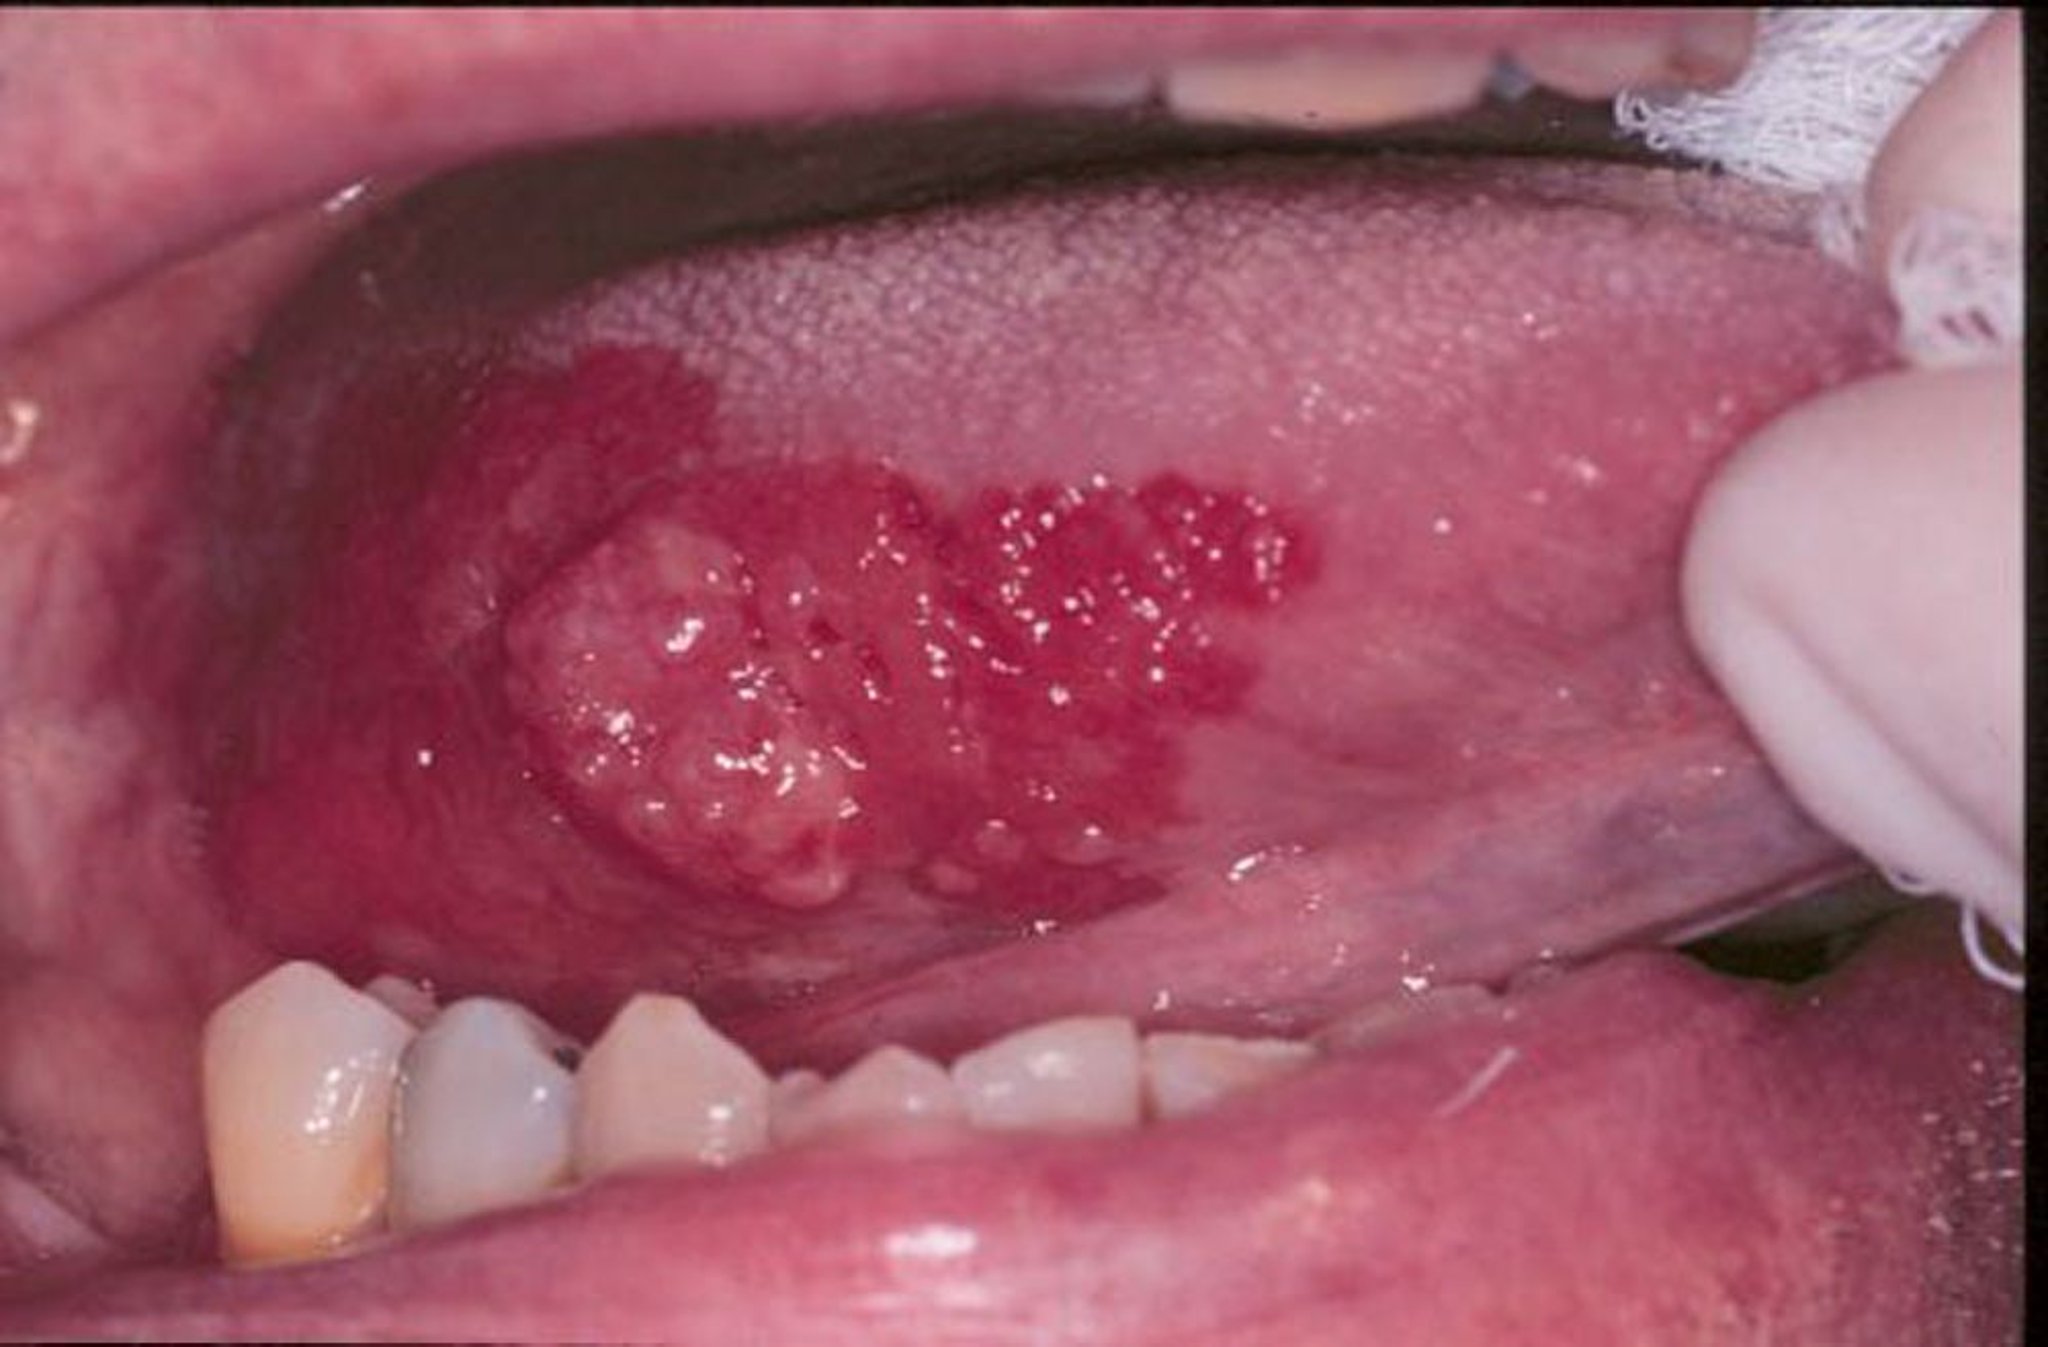

紅板症および扁平上皮癌

紅板症とは,口腔内に発生するビロード状の病変で発赤があるもの,平坦なもの,びらんを呈しているものを総称する用語である。この画像では,舌上の外方増殖性の扁平上皮癌の周囲に紅板症がある。

Image provided by Jonathan A.Ship, DMD.